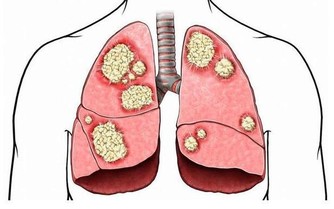

❶ 、【功能主治】養陰清肺,化痰益氣。用於肺熱燥咳、陰虛勞嗽、乾咳痰粘、氣陰不足、煩熱口乾。

❶、【性味】甘苦淡,涼。 ❷、【歸經】 入肺、脾經。 ❸、【功能主治】 養陰清肺,益胃生津。用於肺熱燥咳、勞嗽痰血、熱病津傷口渴。 10石斛

❶、【功能主治】養陰潤肺,清心安神。用於陰虛久咳,痰中帶血,虛煩驚悸,失眠多夢,精神恍惚。具有養陰潤肺止咳功效,用於肺陰虛的燥熱咳嗽,痰中帶血,如百花膏。治肺虛久咳,勞嗽咯血,如百合固金湯。具有清心安神功效,用於熱病餘熱未清,虛煩驚悸,失眠多夢等。藥用時煎服,10~30g。清心宜生用,潤肺蜜炙用。 ❷、【功效】養陰清熱,滋補精血。 16玉米須 玉米須味甘、淡,性平;歸腎、肝、膽經;質輕滲降;具有利尿消腫,平肝利膽的功效;主治水腫,小便淋瀝,黃疸,膽囊炎,膽結石,高血壓病,糖尿病,乳汁不通。有利尿降壓功能。 廣告 - 請繼續往下閱讀 17紅豆 ❶、【性能】味甘,性平。能健脾利濕,散血,解毒。 ❷、【用途】用於水腫、腳氣;產後缺乳,腹瀉、黃疸或小便不利;痔瘡,腸癰。 18杏仁

富含蛋白質、脂肪、糖類、胡蘿蔔素、B族維生素、維生素C、維生素P以及鈣、磷、鐵等營養成分。其性苦微溫,有小毒,滋潤養肺通便。適用於陰虛肺熱、咳嗽、咽乾舌燥、大便乾結者。 19羅漢果

廣告 - 請繼續往下閱讀 其性甘涼,清熱潤肺止咳通便。 20紫蘇